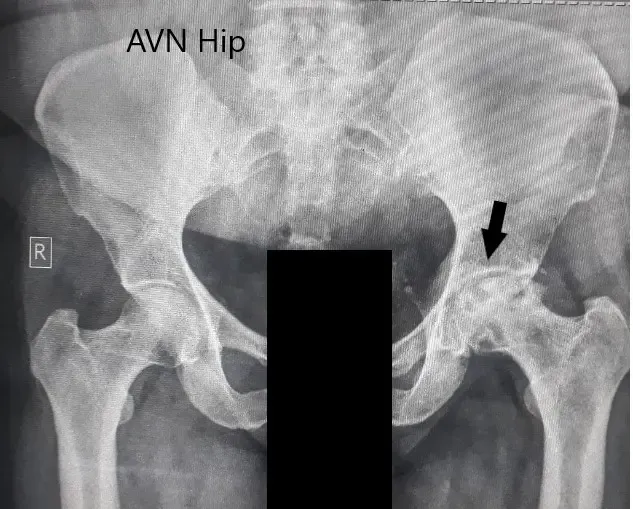

Se obtuvo una radiografía que sugería una pérdida severa de espacio articular con cambios en acetábulo en la cadera izquierda. Se perdió el contorno esférico de la cadera izquierda. Esclerosis y quistes subcondrales estaban presentes en la cadera izquierda con colapso.

Radiografía preoperatoria de la pelvis con ambas caderas en vista anteroposterior que muestra cambios en el AVN en la cadera izquierda.